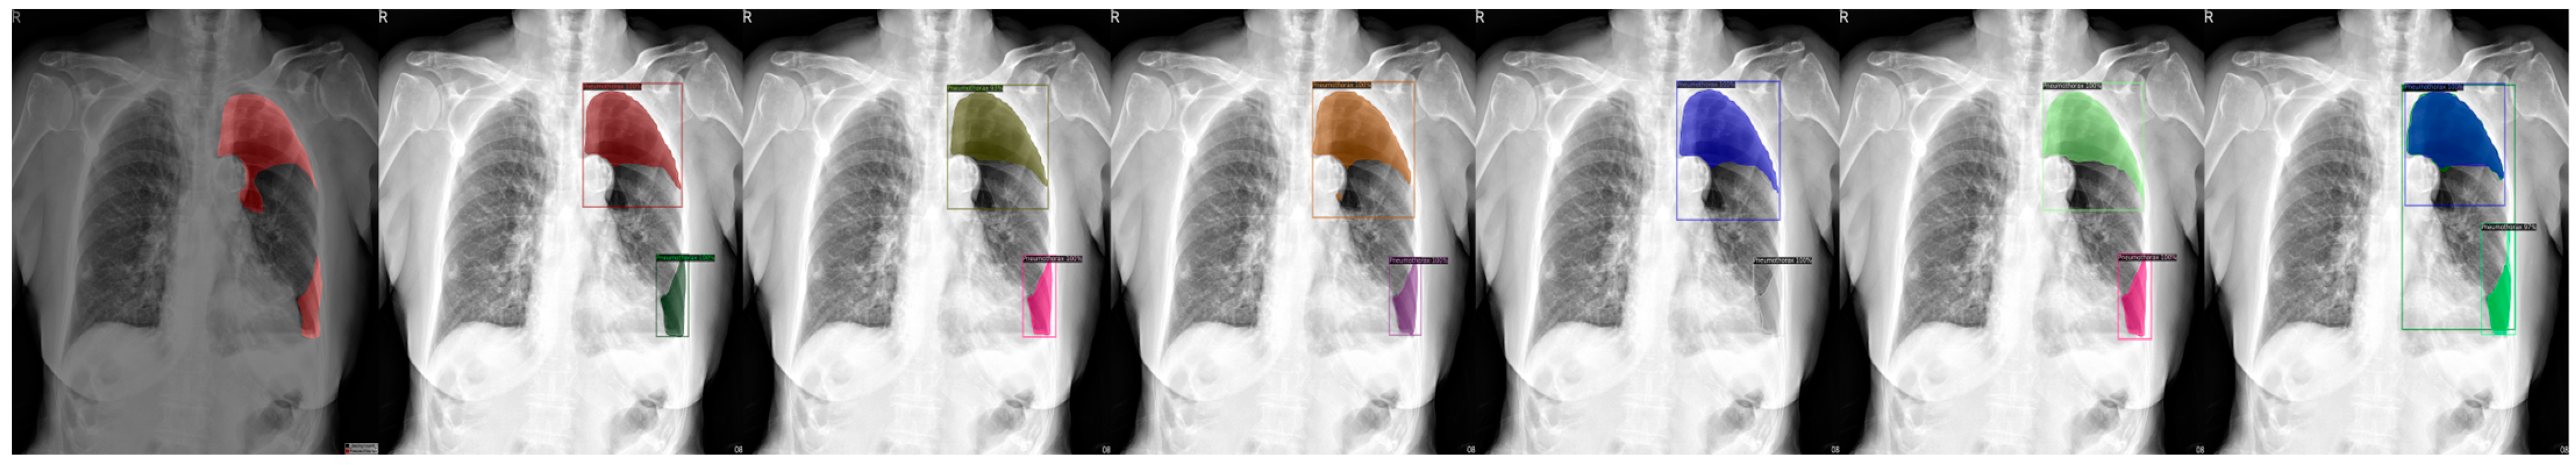

| Transfer Learning Model | False Positive (%) | False Negative (%) | Accuracy (%) | AP (%) | AP50 (%) | AP75 (%) |

|---|---|---|---|---|---|---|

| ResNet50 (COCO) | 1.33 | 4.38 | 94.29 | 48.76 | 80.34 | 53.35 |

| ResNet101 (COCO) | 1.09 | 3.68 | 95.23 | 46.82 | 76.61 | 50.46 |

| ResNeXt101 (COCO) | 0.88 | 3.44 | 95.68 | 44.61 | 78.95 | 49.20 |

| ResNet50 (LVIS) | 1.47 | 5.91 | 92.62 | 49.26 | 84.20 | 53.45 |

| ResNet101 (LVIS) | 1.12 | 4.99 | 93.89 | 51.57 | 79.46 | 61.40 |

| ResNeXt101 (LVIS) | 1.05 | 3.40 | 95.55 | 49.50 | 82.20 | 50.79 |